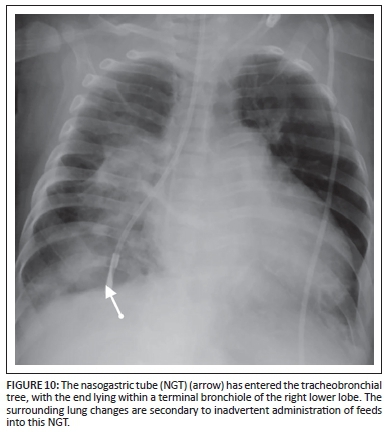

Nasogastric tube (NGT)

Uses: The NGT is inserted for the aspiration of gastric contents, gastric decompression or feeding the patient. The tip should lie within the stomach.

Complications

The NGT can be misplaced in the tracheobronchial tree (Figure 10). Perforation of the oesophagus or stomach is extremely uncommon, but can occur, particularly in premature infants.7 A coiled NGT in a proximal oesophageal pouch is important to recognise in oesophageal atresia.2 In neonates with left-sided congenital diaphragmatic hernia, the NGT tip is most commonly positioned at the gastro-oesophageal junction or within the left hemithorax. An NGT deviating to the right is seen in a patient with heterotaxy syndrome and abdominal situs (Figure 11).